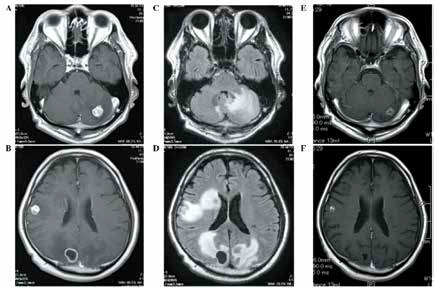

EGFR-TKI一线治疗患者 MRI颅脑随访模式不影…

EGFR-TKI一线治疗患者 MRI颅脑随访模式不影…

中国台湾研究者Shen等报告,EGFR-TKI一线治疗EGFR突变型肺腺癌患者时,无论是否存在初始的脑转移,颅脑MRI规律随访或不规律随访均不显著影响结局。(Lung Cancer. 2019年10…